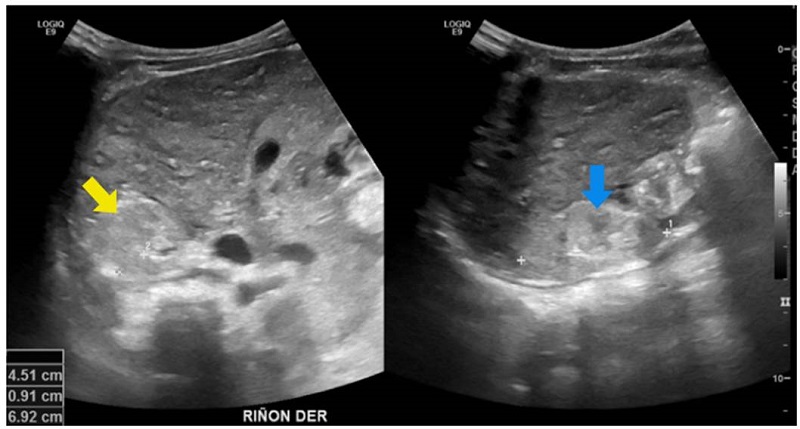

Se trató de un paciente de sexo masculino, asintomático, con antecedente de padre con enfermedad poliquística renal y enfermedad renal crónica en estadio IV 23. El seguimiento se inició a los cuatro años de vida con pruebas de función y ecografías renales periódicas. Las ecografías mostraron inicialmente un quiste cortical simple con subsecuente aparición, en nuevas imágenes, de masas quísticas bilaterales con aumento de tamaño (figura 6). Tiene una hermana en seguimiento por el mismo antecedente, también con progresión de lesiones quísticas sin deterioro de la función renal. El paciente continuó con seguimiento institucional hasta el año 2021 (ocho años de vida), momento en el que se encontraba en trámite la autorización por parte de la entidad para la valoración genética.

Análisis. La enfermedad poliquística renal autosómica dominante es causada principalmente por variantes patogénicas de los genes que codifican para policistinas, PKD1 (80 % de los casos) o PKD2 (15 %) 22. Estos genes codifican para receptores que interactúan entre sí y que son importantes en la regulación de las concentraciones de calcio y la traducción de señales extracelulares en el cilio primario 24. Además de sus manifestaciones renales, la enfermedad poliquística renal autosómica dominante se caracteriza por un espectro de manifestaciones extrarrenales -incluyendo enfermedad poliquística hepática y aneurismas intracraneales, entre otras-, por lo que es una enfermedad de compromiso sistémico 22,25. El diagnóstico etiológico de la esta enfermedad es importante porque permite un adecuado seguimiento y la búsqueda de otras manifestaciones de la enfermedad, así como la identificación y tamizaje de familiares en riesgo 26.